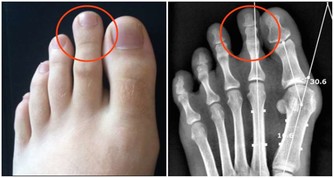

隨著夏季的到來,天氣漸漸炎熱,很多人穿上了涼鞋、夾板,使得腳步和趾部長期暴露在外界環境中。人體的腳部和腳趾部在日常生活中接觸外界較多,在勞動中受傷的機會也比較多,腳指甲極易受到損傷。加上夏季溫度比較高,受傷的部位極易受到病毒侵染,發生感染,腳溝炎便是其中的一種。

一、腳溝炎是什麼?

腳溝炎,是指腳指甲在受到外界的擦傷、刺傷、割傷後。因為沒有得到及時的處理,而受到局部的感染,細菌堆積,導致甲下發生膿腫,這是腳溝炎最主要的病因。此外,趾甲剪得太短或長期不剪趾甲、長期穿不合適的鞋子也會造成腳溝炎的發生。